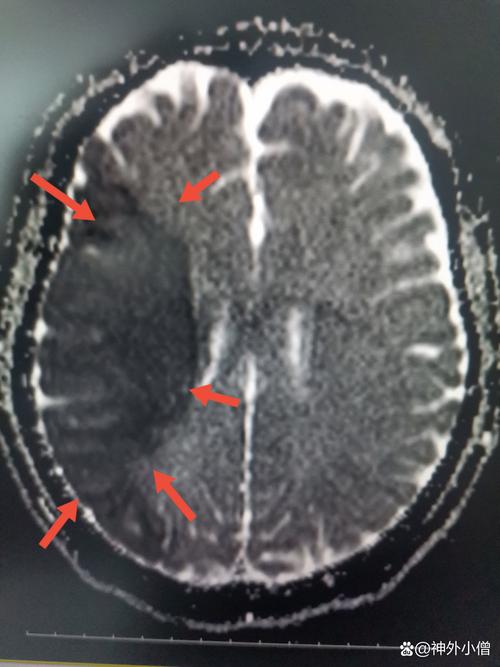

“侧脑旁”这个描述指的是病变位置紧邻侧脑室,这个位置的脑梗之所以严重,主要有以下几个关键原因:

- 梗塞面积大小: 梗塞范围越大,症状越重,预后越差,CT或MRI上显示的梗塞体积是判断预后的重要指标。